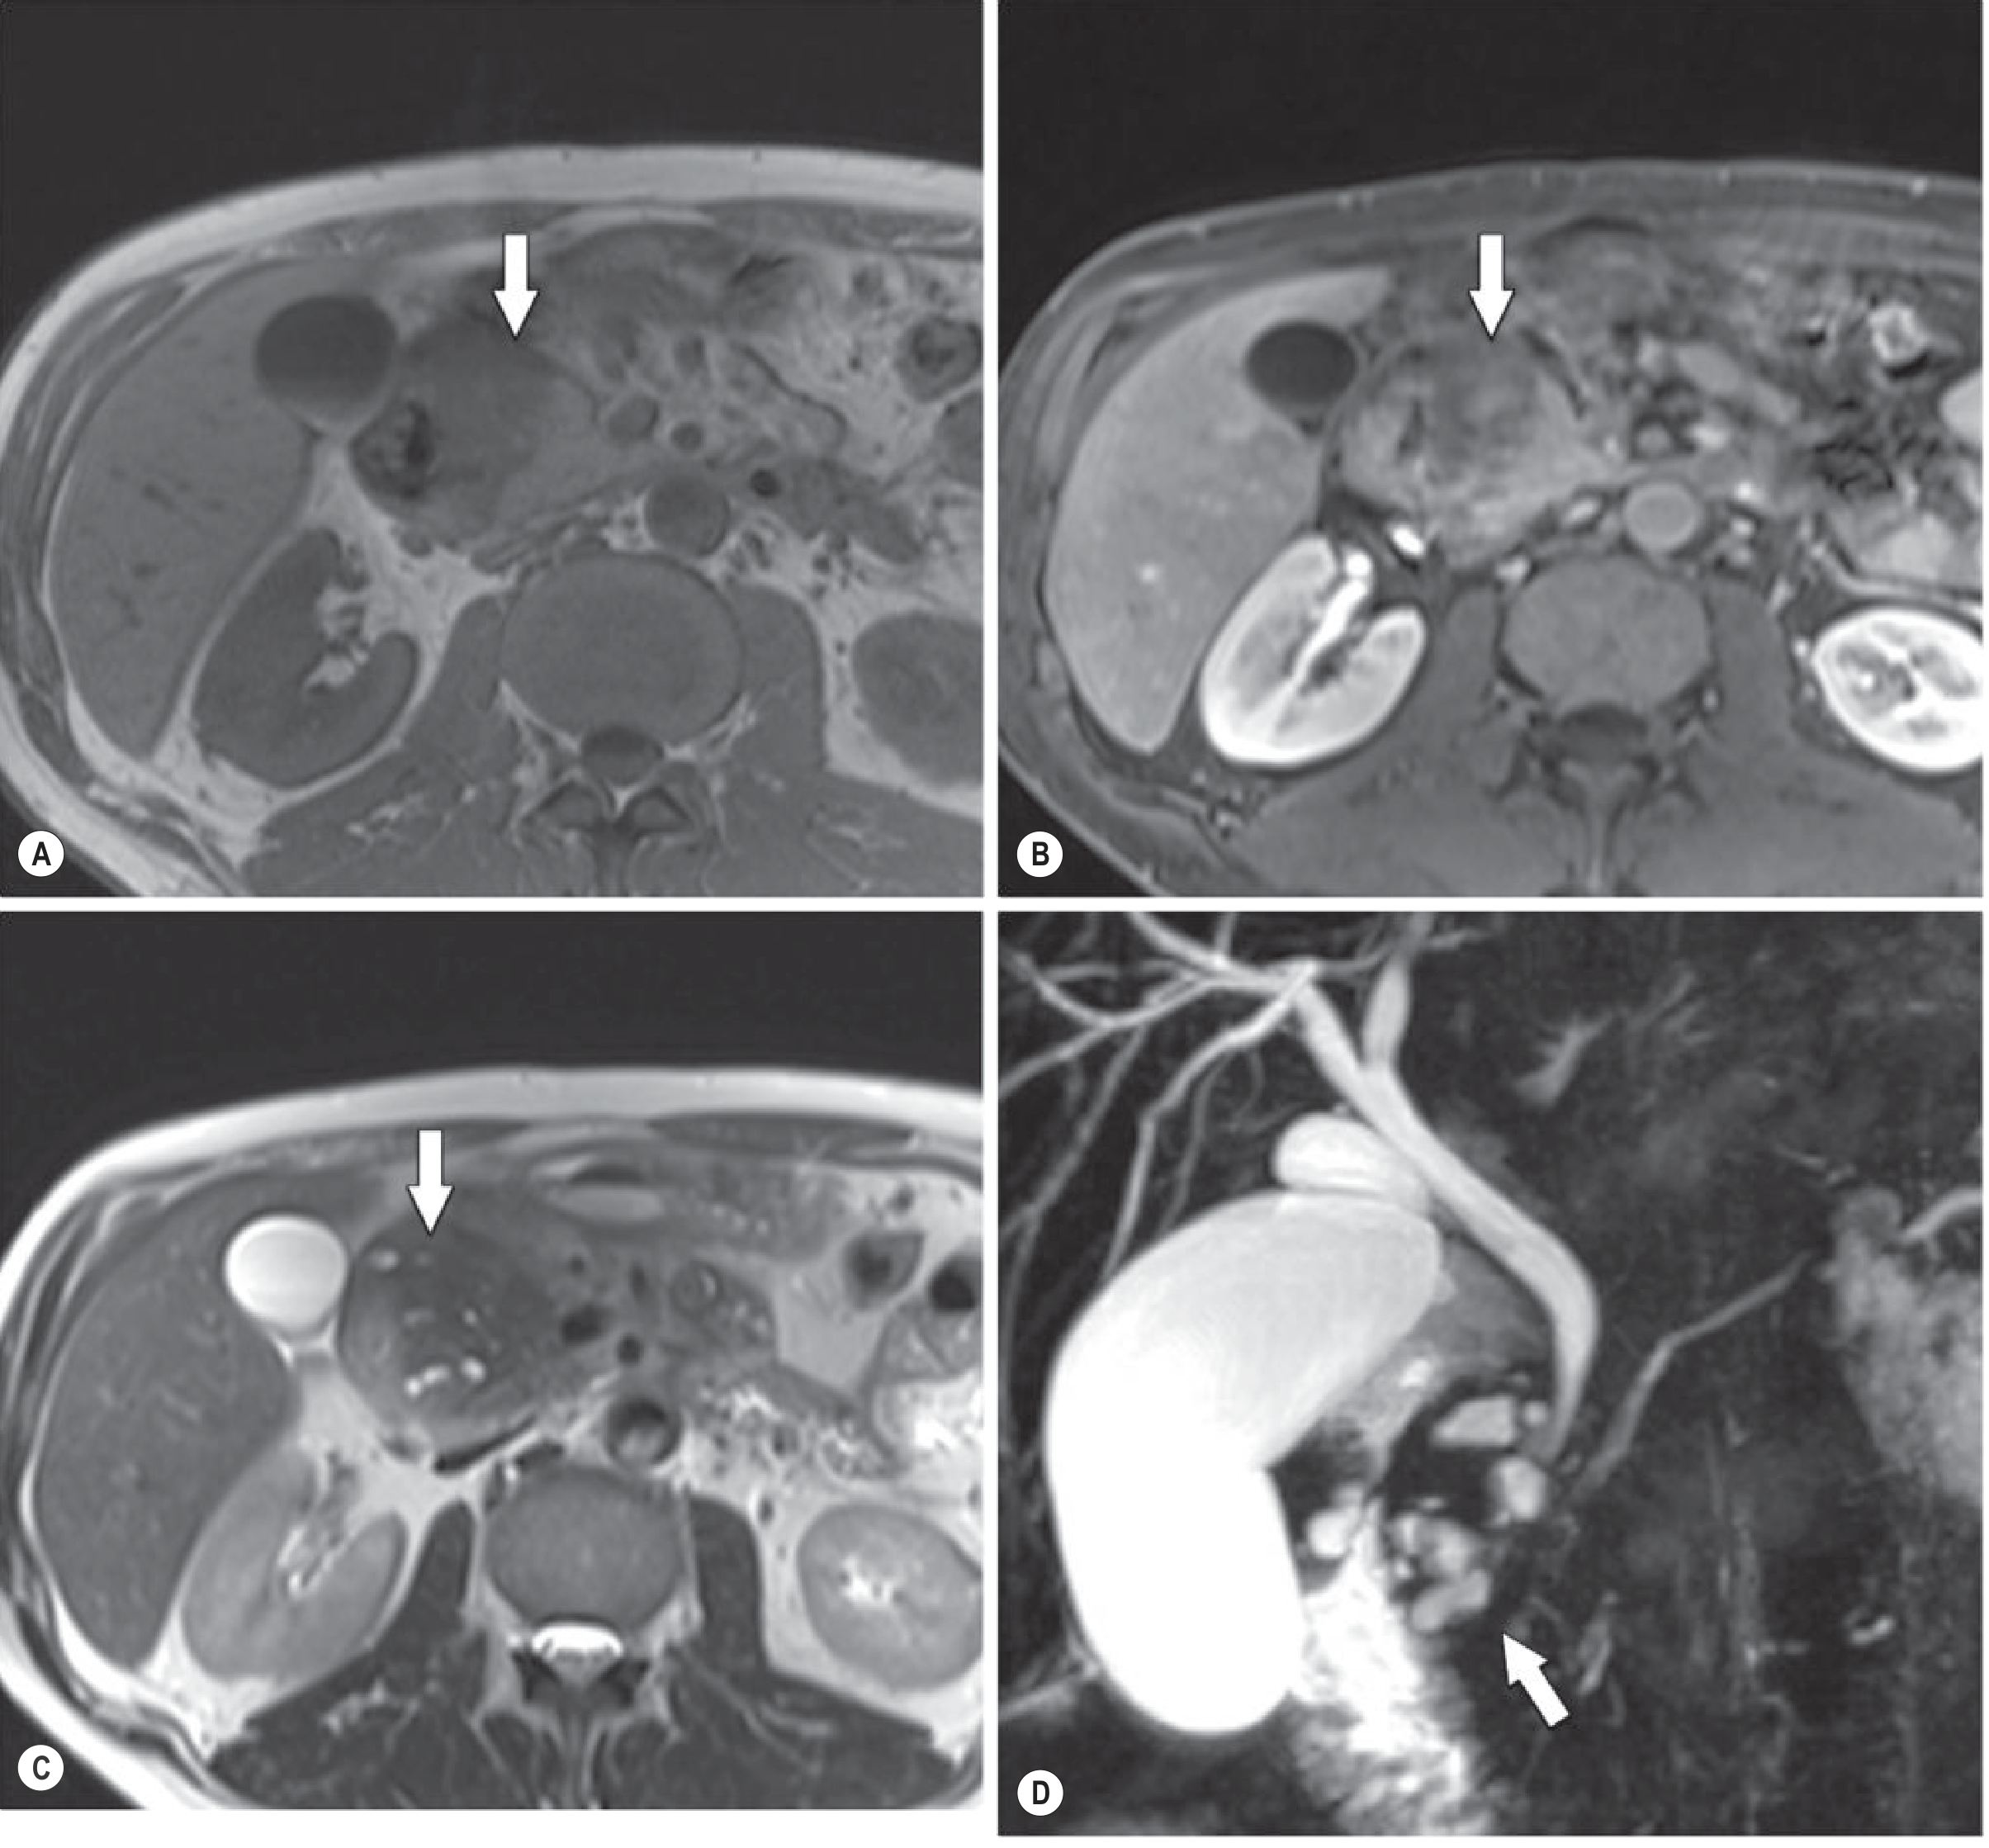

Fig. 25.23A (Grainger & Allison's) — CT showing the low-density groove mass (arrows) between the pancreatic head and duodenum (D):

CT groove-predominant paraduodenal pancreatitis — low-density mass between pancreatic head and duodenum

Fig. 25.24 (Grainger & Allison's) — Segmental form: T1 in-phase (A) and gadolinium-enhanced T1 (B) show a large mass involving the pancreatic head (arrows); T2 (C) shows multiple small cysts in the groove and head; MRCP (D) delineates the cysts clearly (arrow):

MRI of segmental paraduodenal pancreatitis — large mass with cysts in groove and pancreatic head

• Groove-predominant form: plate-like, hypoattenuating (low-density), poorly enhancing lesion situated between the pancreatic head and the descending duodenum (labeled "D" in the CT below — arrows point to the mass)

• Diffuse stranding and inflammatory changes surrounding the first portion of duodenum

• A curvilinear or cystic fluid collection in the groove — subtle but classic for groove pancreatitis

• Pancreatic and/or bile duct dilatation may be present

• The main pancreatic parenchyma is largely unaffected (groove-predominant form)

• Segmental form: the low-density mass extends into and involves the pancreatic head — difficult to distinguish from carcinoma

• T1 GRE fat-suppressed: hypovascular (low signal) plate-like mass in the groove

• T2-weighted TSE: pathognomonic small cystic changes within the groove mass and in the duodenal wall — this cystic pattern is what distinguishes it most clearly from cancer

• MRCP additionally shows the cysts and any associated ductal changes